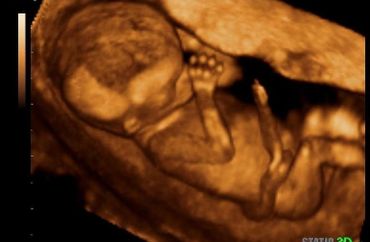

All our providers do their own ultrasounds in the office during your visit. We are known for our ultrasounds and do at least four with each pregnancy. And we can record your ultrasound on a USB device for you to take home and share!